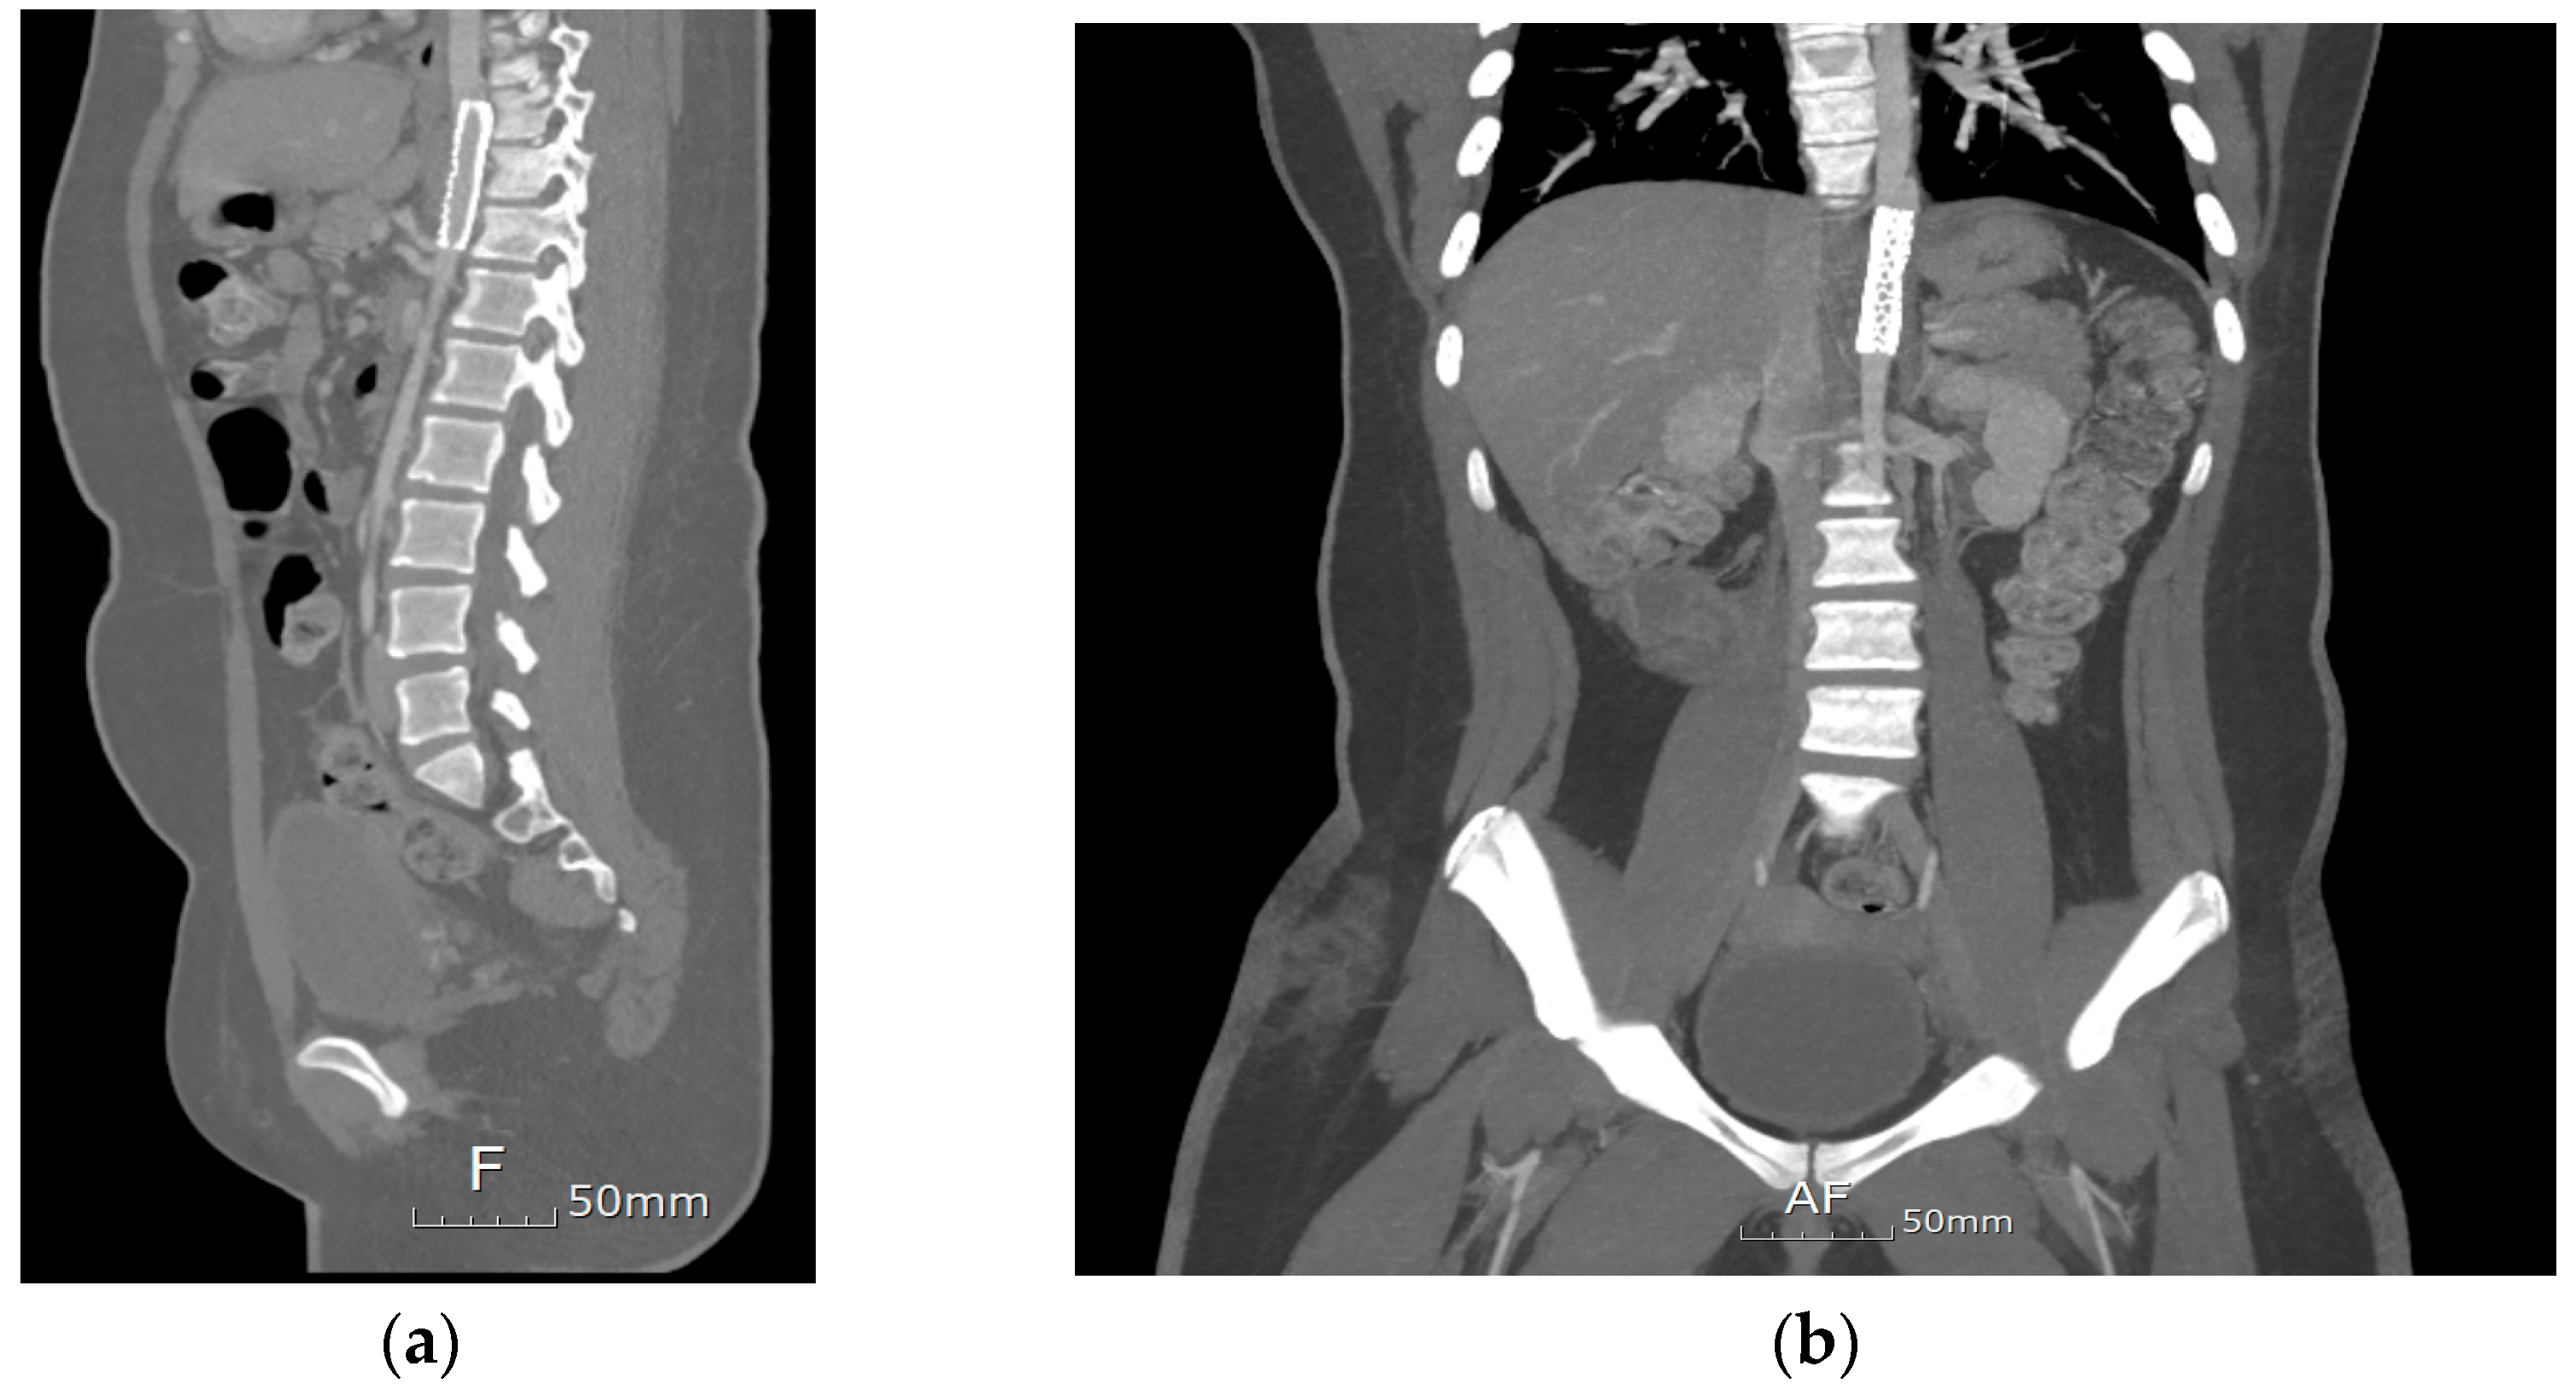

A metal stenting procedure was performed after a thorough discussion with the cardiothoracic surgical team. Left heart catheterization was performed. Angiography showed stenosis in the descending aorta, with a waist diameter of 8 mm, an upper 20 mm, and a lower 15 mm (Figure 2a). A systolic pressure gradient of 40 mmHg was noted across the stenotic segment (blood pressure above the stenosis, 110/65 mmHg; below the stenosis, 70/60 mmHg). The patient was placed under general anesthesia. First, balloon angioplasty was performed using Powerflex (Powerflex Pro, Cordis, Miami, FL, USA) 6.0 × 80 mm, then 8.0 × 100 mm, and finally Mustang (Boston Scientific, Marlborough, MA, USA) 9.0 × 40 mm. Despite this procedure, residual stenosis with a systolic blood pressure drop greater than 30 mmHg across the stenotic portion remained (blood pressure above the stenosis 110/70 mmHg; below the stenosis). A 12 mm (5.5 cm) Andrastent XXL aortic stent (AndraMed GmbH, Reutlingen, Germany) was deployed (inflated by a balloon at 7 atm pressure) and successfully inserted into the descending aorta (Figure 2b). The trans-stenotic pressure gradient decreased significantly to 5 mmHg. Post-procedure CT showed significant improvement; however, a mild residual waist circumference was present at the T10 level (Figure 3). After stent implantation, the limb BP discrepancies decreased (U/E 120/65 mmHg and L/E 115/56 mmHg). The patient was discharged on postoperative day 3. During the months-long follow-up period in the outpatient setting, the patient had no other complications.

Figure 3. A stent has been placed in the descending aorta at the T9–T11 level. (a) Sagittal view (b) Coronal view. The focal stenosis of the descending aorta was successfully treated with stent insertion.